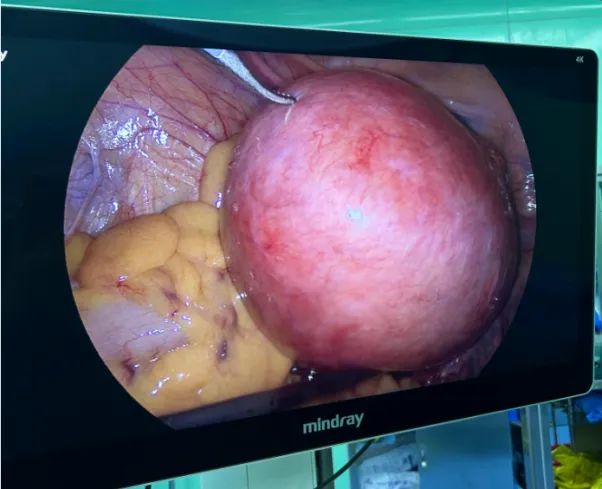

手术前后对比图

手术前

手术后

熊贻海主任带领团队第一时间开展病情评估:该肌瘤体积大,不仅引发经期异常,且患者尚未绝经,肌瘤后续仍有生长风险,而腹腔镜手术虽具备微创优势,但巨大肌瘤会导致盆腔操作空间狭小,给手术带来不小挑战。在与患者充分沟通后,遵循患者保留子宫意愿,团队最终确定采取腹腔镜微创剔除方案。手术中,团队凭借微创技巧精准剥离肌瘤、松解粘连,把控止血,出血少,通过微小切口取出11cm巨大肌瘤,实现“微创除瘤、保留子宫”双重目标。术后科室采用加速康复护理模式,精细化护理助力患者快速恢复。